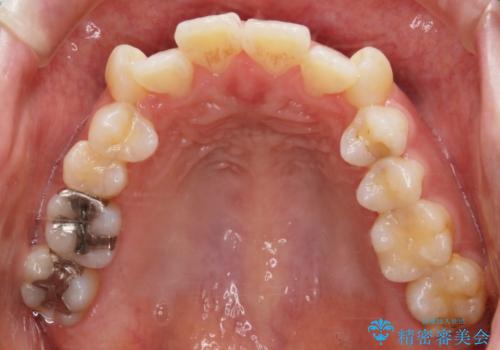

- 前歯のガタつき・噛み合わせの不調を主訴にご来院されました。

患者様のお仕事柄、目立たない装置で矯正したいとのご要望があり、今回はインビザラインを用いて抜歯矯正を行うこととなりました。

本来、抜歯によって得られる大きなスペースのコントロールはワイヤー装置の方が得意とされていますが、こちらの患者様のように犬歯が大きく手前に傾斜していて奥歯の噛み合わせにそれほど問題がないケースではマウスピース装置でも十分にコントロールできることが予測されます。